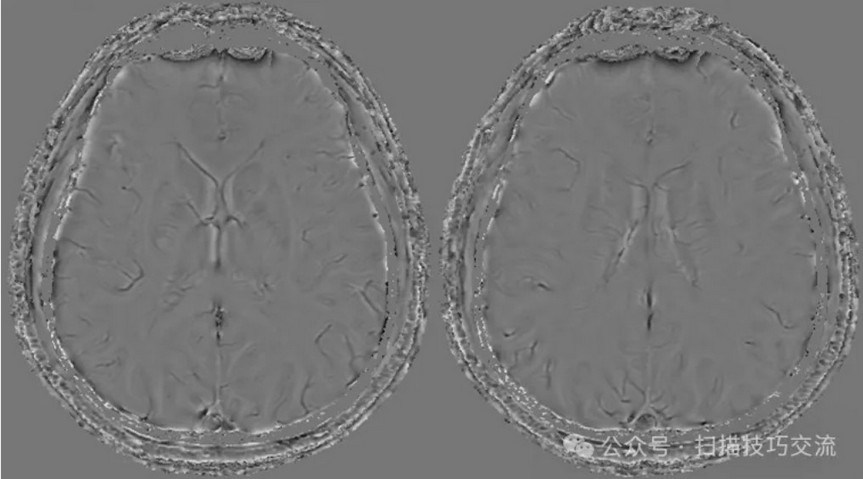

临床申请:颅脑平扫,静脉成像,磁敏感成像,颅内静脉血管黑血成像。

SWAN未见异常。